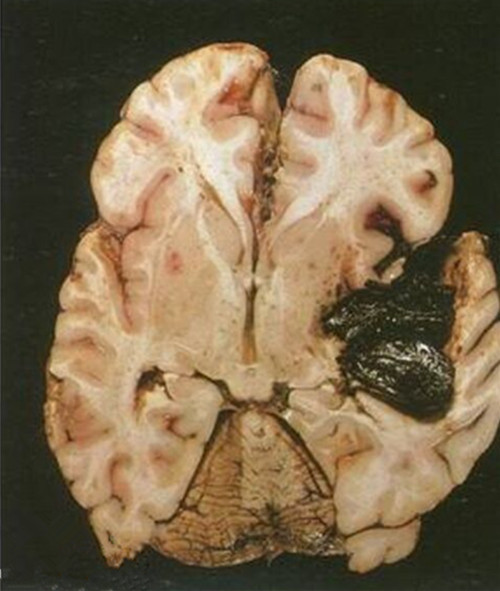

細菌性的腦膜炎的

細菌性的腦膜炎

細菌性腦膜炎的解剖

腦膜炎細菌性的腦部的

腦膜炎細菌性的腦部